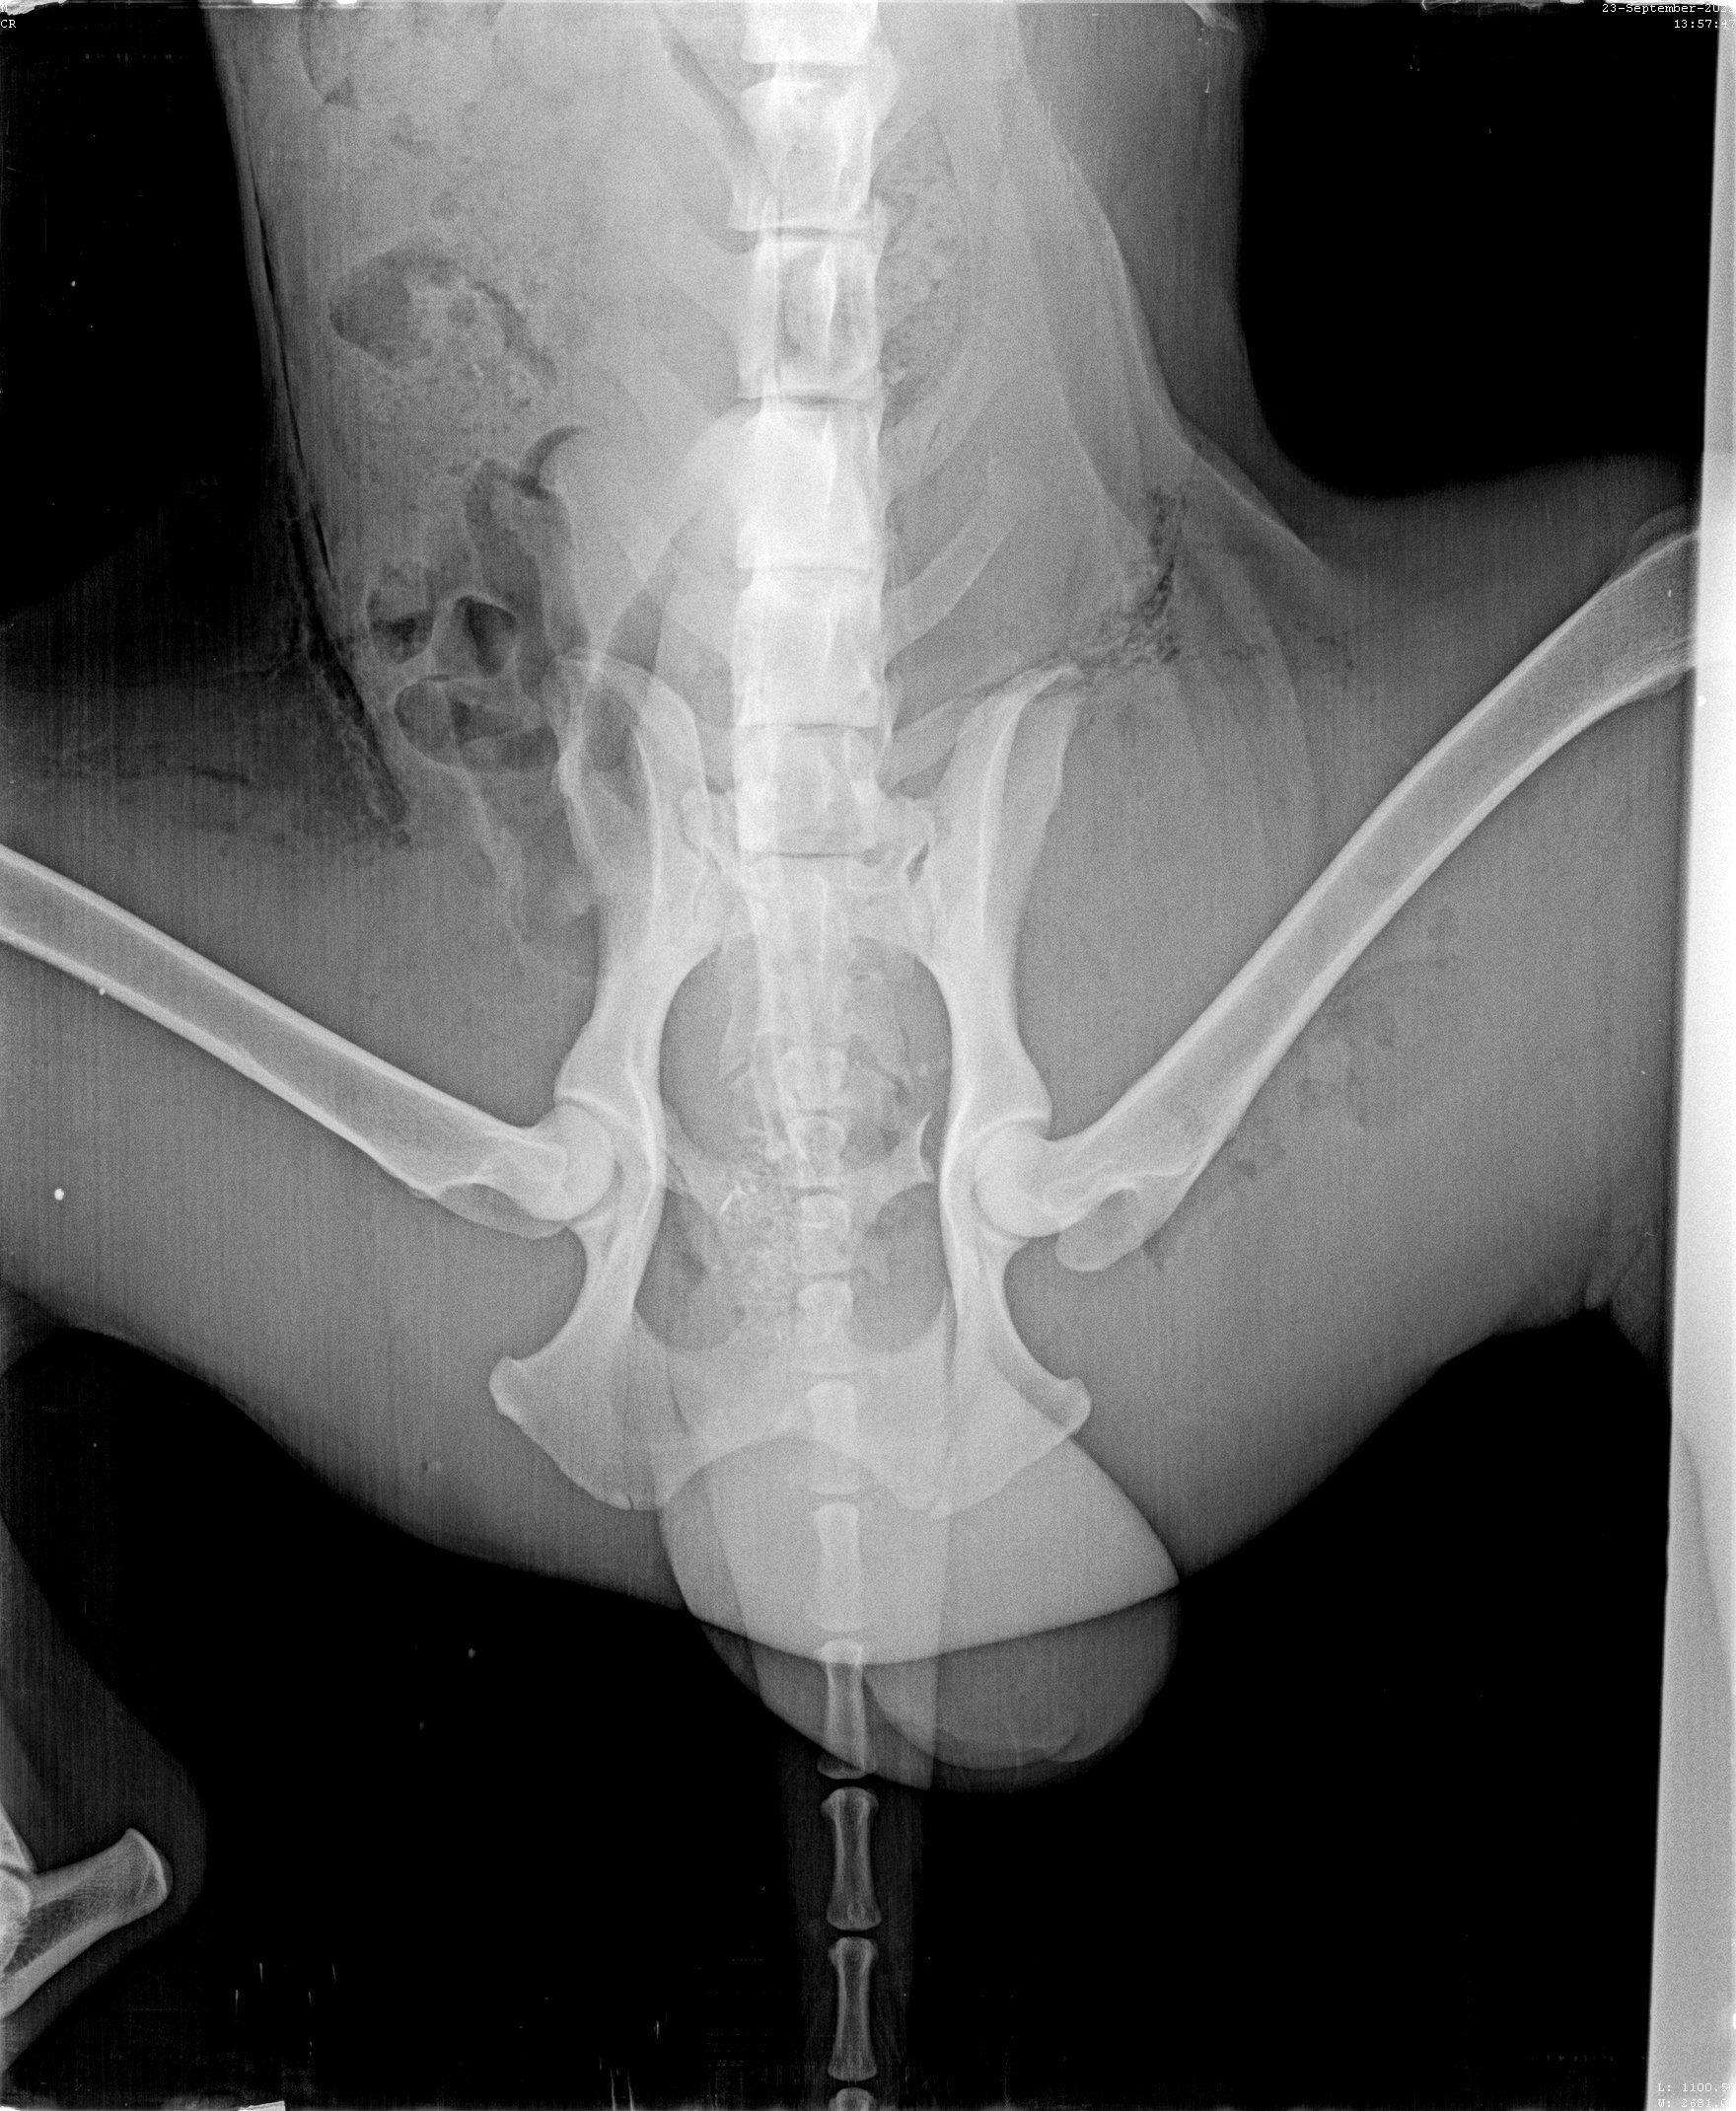

Oktober 2022

Update zu Kilian

Kilian war angefahren an der Autobahn aufgefunden worden. In der Klinik, wo er drei Tage verbleiben musste, da die offenen Wunden gereinigt werden mussten und sein linkes Bein Sorgen bereitete. Die Lähmungen sind wohl zurückzuführen auf den gebrochenen dritten Lendenwirbel, der niedriger lag als die Wirbelsäule. Dies bedeutet Ruhe halten, eine OP kann folgen müssen. Die offenen Wunden am Hinterleib sowie am Hodensack waren äußerst schmerzhaft, so wird er nun weiter mit Antibiotika und mit Fieber senkenden Mitteln behandelt. Die Kosten belasten unser Budget schon sehr, aber Hilfe hat für uns Vorrang.

Für jede Spende für Kilian sind wir dankbar! Jeder Cent kommt an! 🍀

Kilian - Opfer eines Rücksichtslosen

Angefahren und liegen gelassen worden ist dieser Rüde von Aliki auf dem Weg nach Kavala am Straßenrand gefunden worden. Zusammen mit Richarda ist Kilian ins Krankenhaus gebracht worden wo zuerst einmal die Wunden gereinigt wurden, mehrere offene Wunden mussten genäht werden, ein Beinbruch ist offensichtlich, doch das Röntgengerät war kaputt, so dass hier erst später Genaueres gesagt werden kann. Dieser hübsche Settermix litt unendlich, hoffen wir, dass unsere Hilfe ausreichen wird.

Wer mag sich an diesen Kosten beteiligen und Pate Kilians werden?

Update zu Kilian🐕

Dieser Setter-Mix, der den treffenden Namen Kilian erhalten hat - er braucht wirklich einen Schutzengel- ist direkt zum Arzt gebracht worden, der zuerst einmal sämtliche offenen Wunden desinfiziert hat und damit den ersten Heilprozess angestoßen hat. Nun war das Röntgen-Gerät defekt, weshalb er nun erneut zu einer Klinik gebracht werden musste, um seine Hüfte zu röntgen, da bei dem Autounfall vermutlich nicht nur diese fürchterlichen äußeren Wunden zurückblieben. Kilian verhält sich sehr tapfer, hoffen wir, dass die Hilfe, die er in Griechenland erhält, auch von Deutschland aus weiter unterstützt wird. 💕Wer mit einer (einmaligen oder monatlichen) Spende Pate dieses Unfallopfers werden möchte, kann dies über folgenden Link! 💙